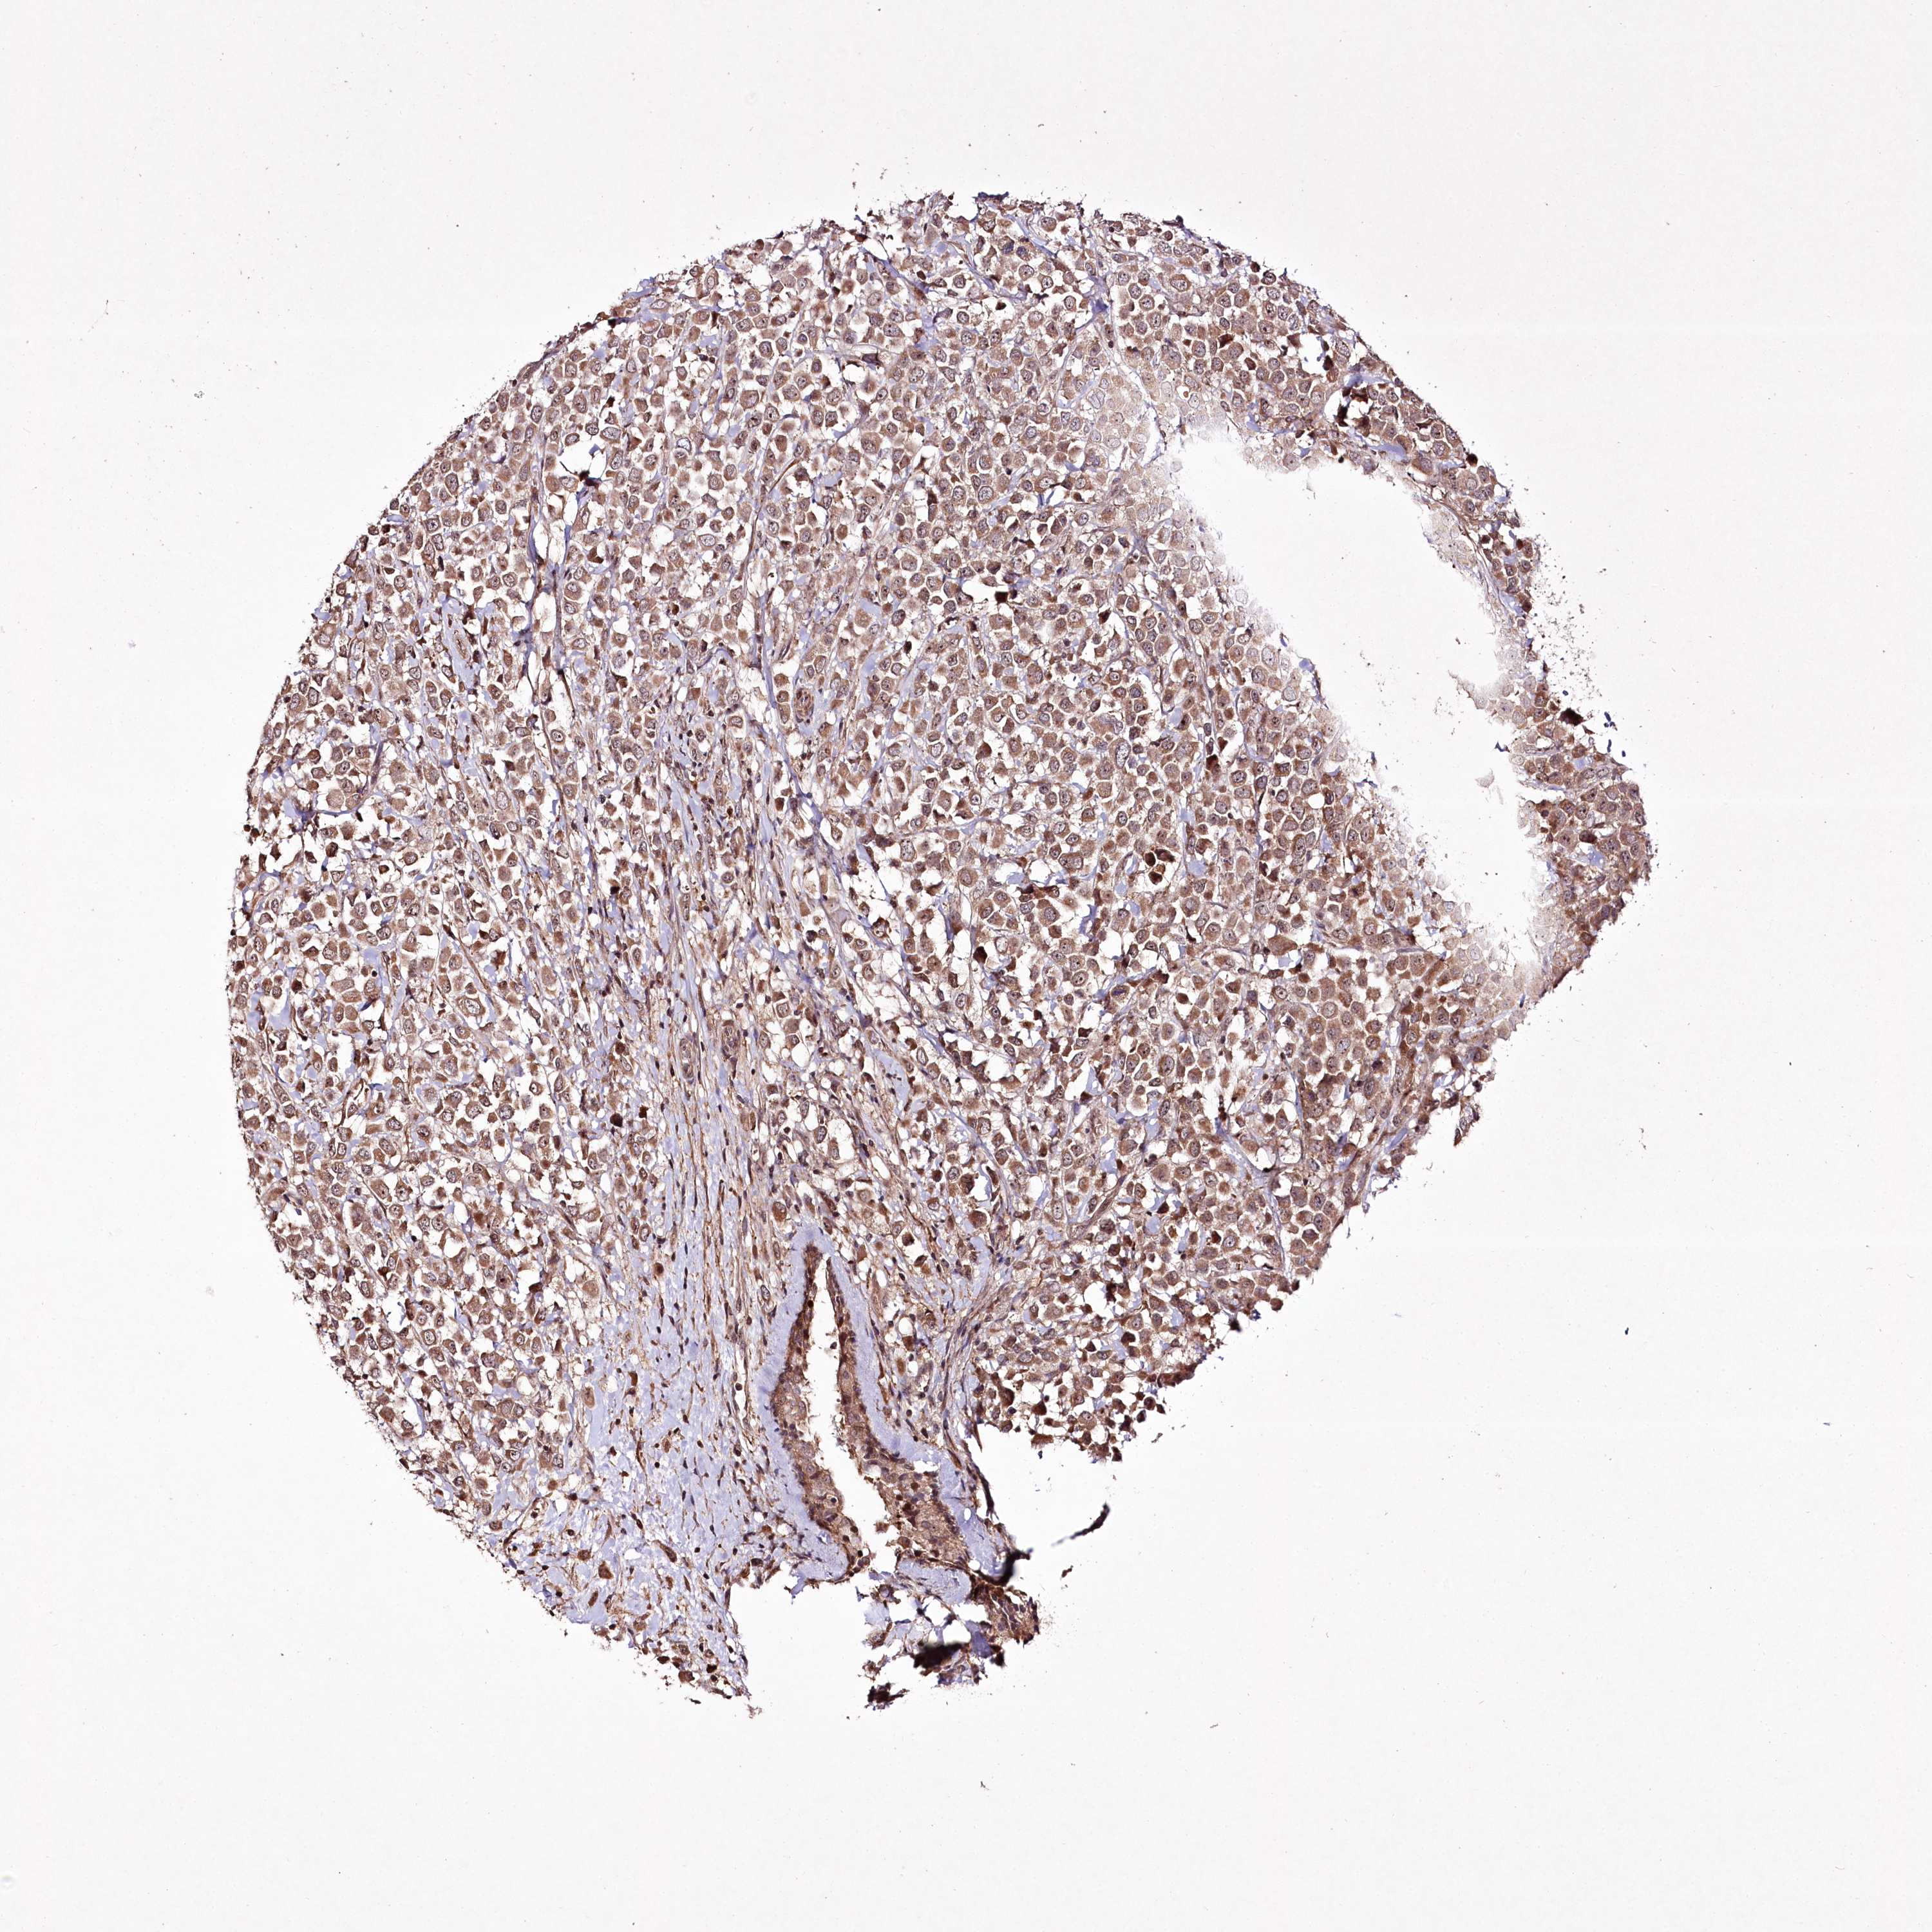

CANCER BREAST CANCER Show tissue menu

BRCA TCGA BRCA VALIDATION PROTEIN EXPRESSION

Breast cancer

Human cancer